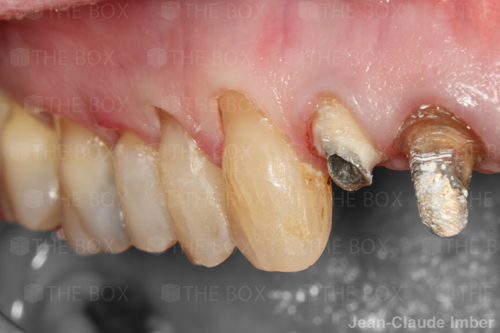

A new case was made public by Jean-Claude Imber check it out here.